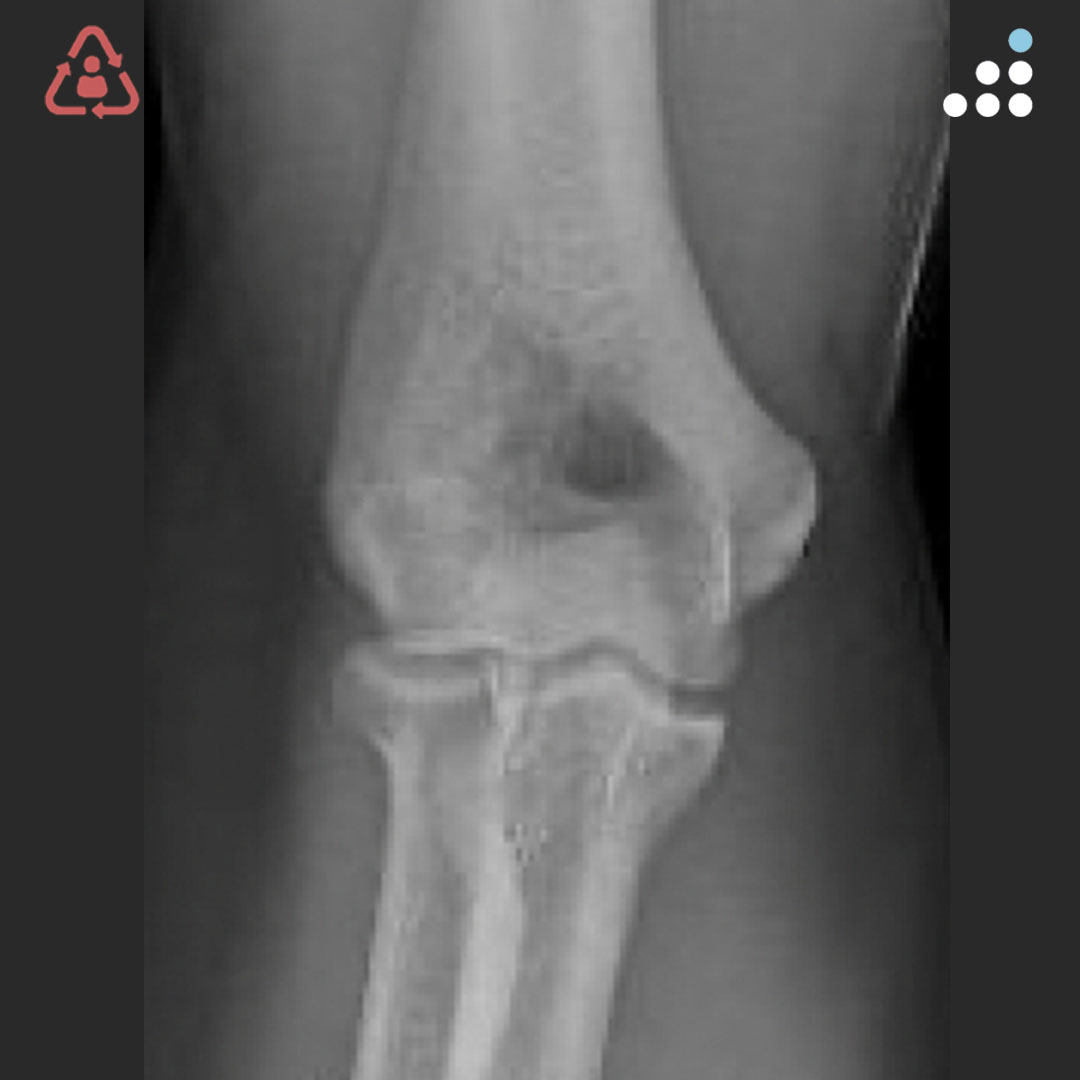

@orthobullets @KPSCALnews @rkh_md @DrMarecek @DeformityDoc @jamesablairMD @FractureDoc @stevemchale @traumaticum @DrFraneNicholas I am concerned about the +Fleck/flake sign. Get MRI or ultrasound to rule out a triceps rupture. If torn, I would perform ORIF and Triceps repair, after restoring the underlying metabolic issues. If the triceps is not torn, then would treat non-operatively.